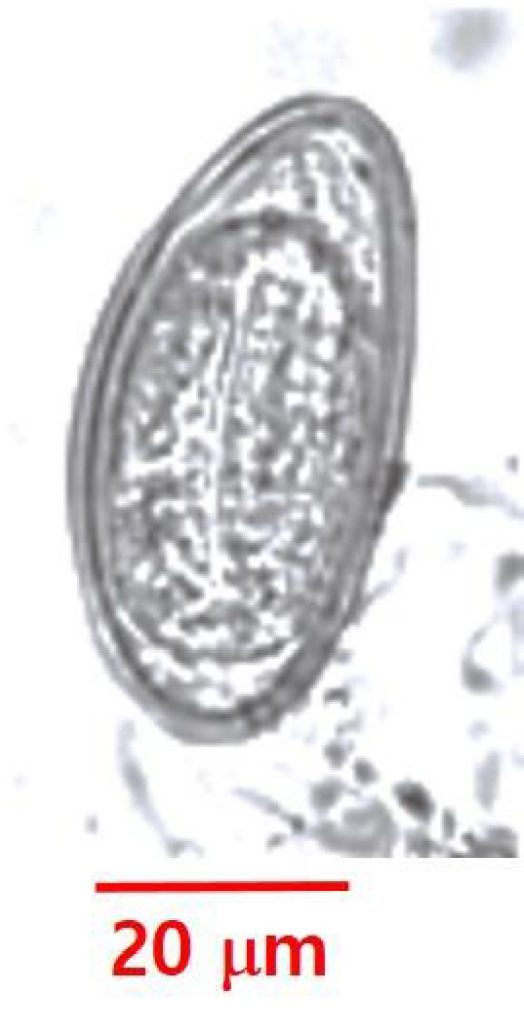

40세 여자가 소화가 잘 되지 않는다고 병원에 왔다. 위 내시경 검사를 시행하던 중 발견된 기생충 사진이다. 이 기생충의 충란은?

• 회충은 크기가 15-35cm로 비교적 큰 편이며, 해바라기 꽃 모양의 수정란을 가진다.

• 사진1: 편충 충란

• 사진3: 요충 충란

• 사진4: 구충 충란

• 사진5: 만손주혈흡충 충란